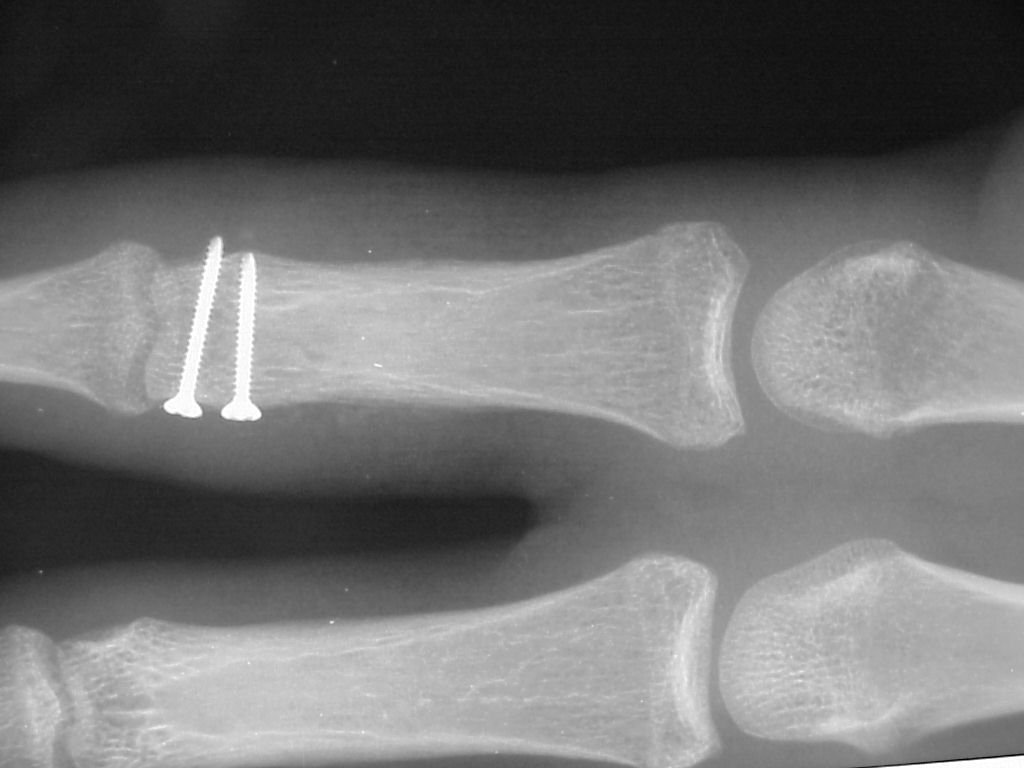

Clinical Example: Unicondylar proximal phalanx head fracture with micro screws

Unicondylar fractures of the phalangeal head are common, frequently unstable and unacceptably displaced. Although some may be treated successfully with percutaneous reduction and fixation, many require open reduction. In these cases, the screws were put right through the collateral ligament and sunk into the cortex. I think the simplest way to do this is to reduce and stabilize with two K wires, then remove the wires and replace with screws, one at a time, so reduction is maintained throughout. 1mm=39/1000" Kwire, so doing the math, here is how you choose the right sized Kwire to use as both drill and provisional fixation:

With two screws, bicortical fixation is not needed. The video below illustrates the steps involved, which are the same with either open or percutaneous fixation.

And another patient.